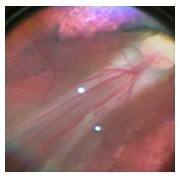

Se consideró como un resultado anatómico desfavorable la presencia de un

pliegue retinal que comprometiera la mácula (Foto

A), un desprendimiento retinal que comprometiera

la mácula (Foto B) o la presencia de tejido retrolental

que impidiera la visualización del fondo de ojo (Foto C).